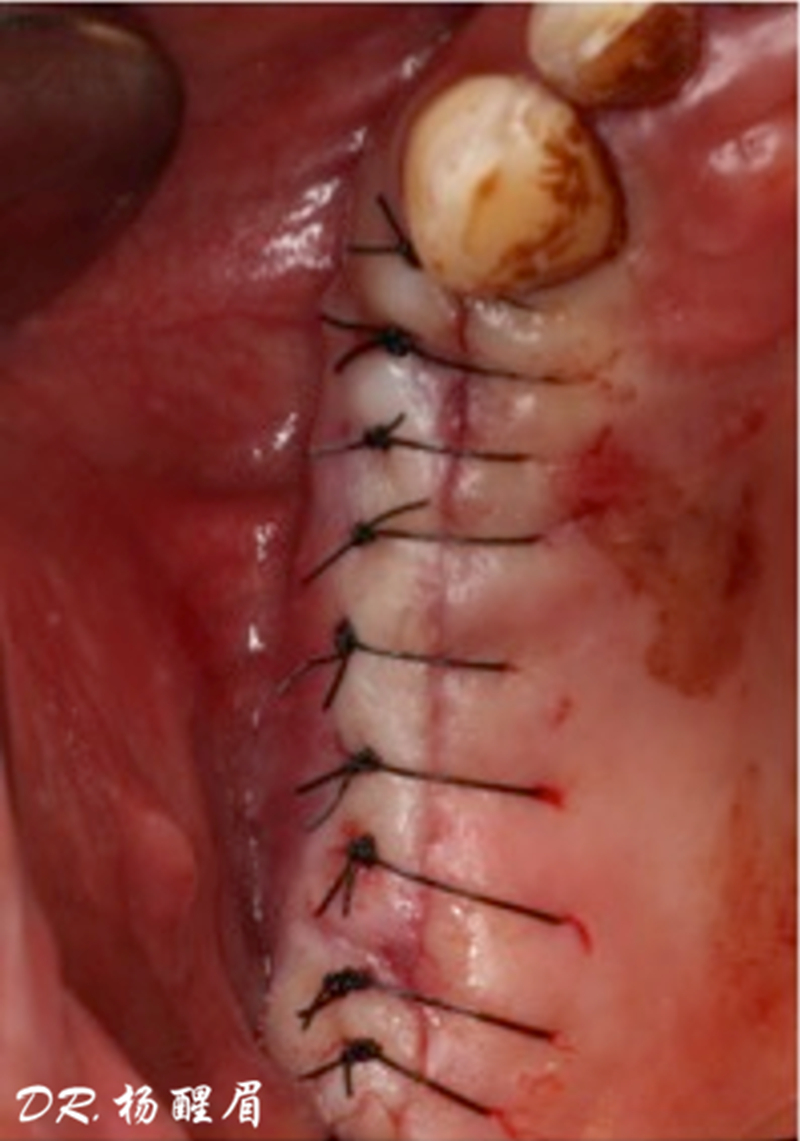

®完成3顆植體的植入,植體位點如術前方案設計,均在同軸線。

®進行縫合